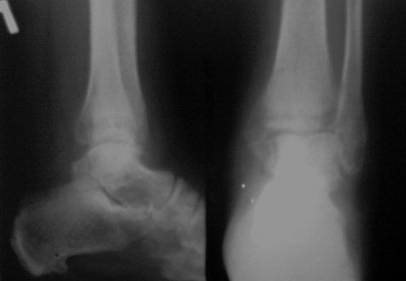

перелом лодыжек трёхмесячной давности

Здравствуйте, коллеги! Ко мне на консультацию обратилась больная 54 года, 110 кг весом.

Травма 3 мес. назад, лечилась амбулаторно в гипсовой лонгете. Как поступить далее? Я планирую ORIF, внутреннюю лодыжку - спицами и проволокой, наружную - пластиной 1\3 трубки. Позиционный винт для фиксации синдесмоза. Как Вы считаете, это верная тактика? какой вероятен исход? Какие имеются нюансы в этом сроке, особенности техники? Может стоит вначале разработать движения в голеностопе? Нужен ли гипс после операции ?С уважением Д.Б.

Правый снимок или размыт, или, что вероятнее - все срослось. Лечите деф. артроз, коллега. А металл, металл в металлолом. Или снимки более четкие. С уважением.

Снимки конечно нечитаемые. Оставлять так конечно нельзя, не устранен подвывих. Но нужно внимательно оченить зоны перелома, т.к. срок достаточно большой. Может так получиться, что вы пойдете на МОС, а найти зоны переломов будет очень сложно, придется отломки разъединять. Хотя в личной практике часто встречаю подобные переломы 2,3,4 мес давности, и когда открываешь - ВООБЩЕ нет признаков сращения, что мне пока непонятно. Если все таки нет сращения рекомендовал бы наружную пластиной с позиционным с концевой резьбой (или рассверлить fibula до ширины резьбы, обязательно зацепившись за внутренний кортикальный слой tibia), а внутреннюю конечно винтом, отломок позволяет. Но есть еще один момент, даже если нет сращения, то зона синдесмоза наверняка уже заполнена рубцовой тканью, поэтому просто затянуть его не получится, нужно или делать ревизию или вообще идти на ВКДО.

Прошу прощения за качество снимков . Во вторник постараюсь сбросить более читабельные снимки + мортиз проекцию . Спасибо за ответ . С уважением Д.Б.